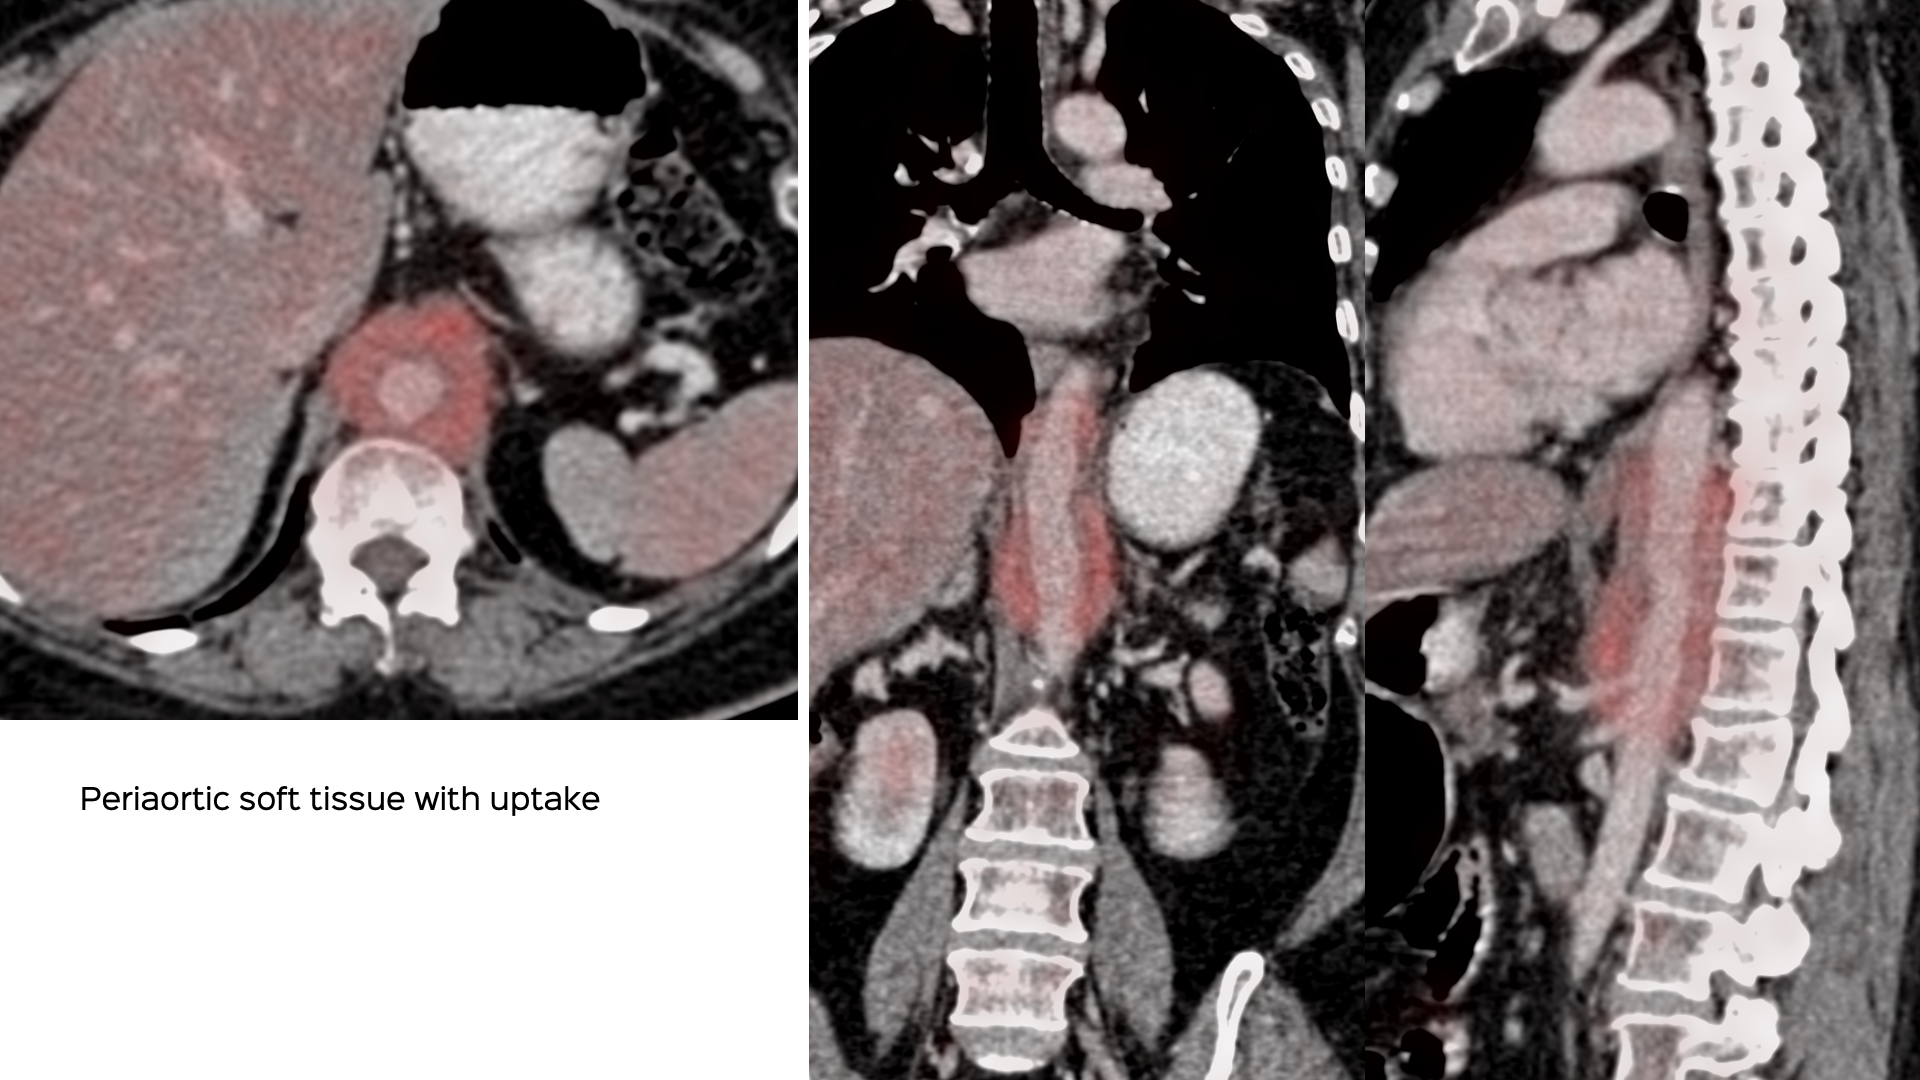

67-years old lady with fever presented with soft tissue encasing the thoraco-abdominal aorta.

This pattern of disease is most common with idiopathic fibrosis, IgG4-related disease.

The rheumatologist and physician, both wanted histopath proof.